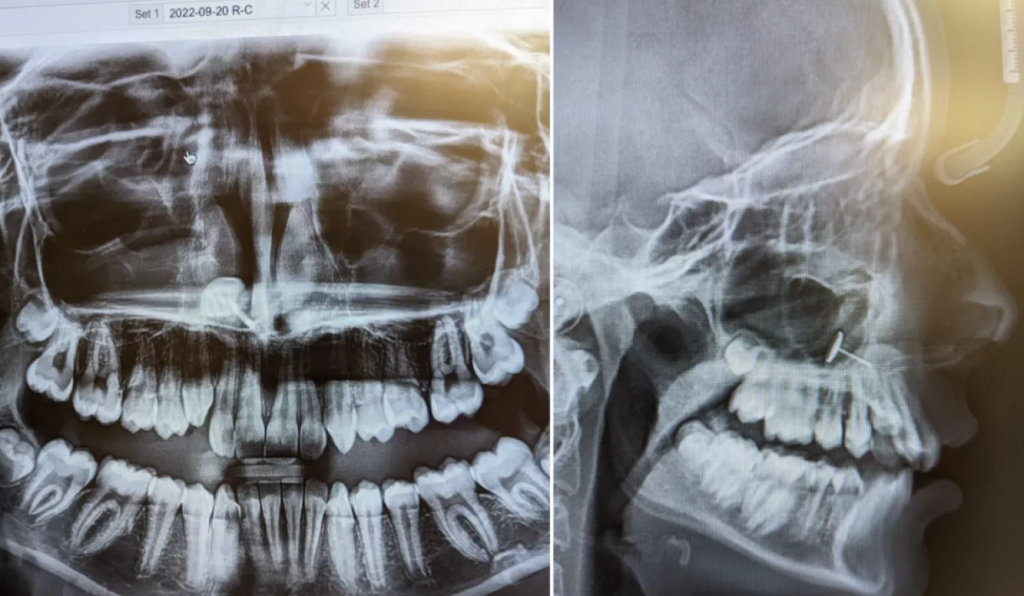

Gjatë kontrollit, ortodonti tregoi radiografinë e gojës dhe të gjithë mbetën pa fjalë: në sinusin e vajzës ishte i ngulur një objekt i vogël metalik.

Nëna nuk kishte asnjë ide se si mund të kishte përfunduar aty, por vajza e dinte të vërtetën. Para gjashtë muajsh, ajo kishte pyetur nëse mund të bënte një shpuarje në hundë, por nëna i kishte thënë se duhej të priste deri në moshën gjashtëmbëdhjetë vjeç. Vajza nuk e pranoi përgjigjen dhe fshehurazi, provoi ta bënte vetë me një vath të zakonshëm.

Duke e shtyrë nga brenda jashtë, në një moment e kishte thithur aksidentalisht dhe vathi ishte ngulur në sinuse. Nga turpi dhe frika, ajo nuk i kishte treguar askujt dhe me kalimin e kohës kishte menduar se ndoshta i kishte kaluar në fyt.

Vetëm pas zbulimit të rastësishëm nga ana e ortodontit, nënës iu desh të kontaktonte një specialist të ORL-së, i cili me pinceta speciale ia hoqi objektin. Fatmirësisht, procedura kaloi pa dhimbje dhe vajza nuk pati pasoja serioze.